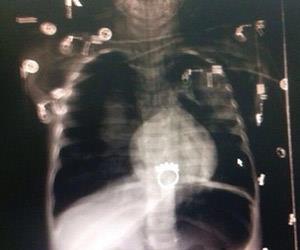

وكان والد الطفلة قد لجأ إلى مستشفى الملك خالد لاستخراج خاتم ابتلعته ابنته قبل أن يقرر الأطباء إجراء منظار لها لاستقرار الخاتم بالمريء، قبل أن يبلغوه بأن المنظار أحدث ثقباً بالمريء، ومن الضروري تثبيت أنبوبين بجانبي الصدر بسبب دخول الهواء لرئة الطفلة وتوقف القلب.

وأضاف أن الطاقم الطبي أخبره بأنهم سيُجرون جراحة ثانية بالمعدة لاستخراج الخاتم الذي سقط واستقر بها قبل أن يخطروه لاحقا بوفاة ابنته، ما جعله يرفض استلام الجثمان بداعي الإهمال والتقصير، ويطالب بالتحقيق في أسباب الوفاة ومحاسبة المقصرين، مشيرا إلى أن ابنته دخلت المستشفى بصحة جيدة تسير على قدميها وتتنفس جيدا.